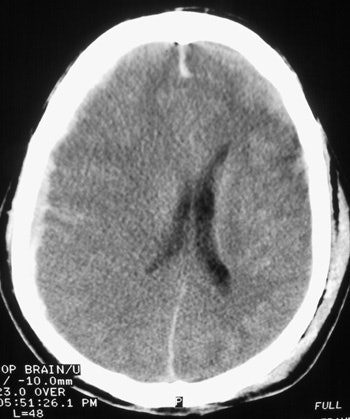

![]() |

| Here, the subdural hematoma (right) is due to venous bleeding on the surface of the brain. This results in a space-occupying lesion with mass effect, shifting brain tissue to the left. The subarachnoid hemorrhage is due to arterial bleeding within the meninges lining the surface of the brain. Both types of bleeding can be seen following blunt trauma to the head. Images courtesy of Dr. John Cameron, University of Miami. |